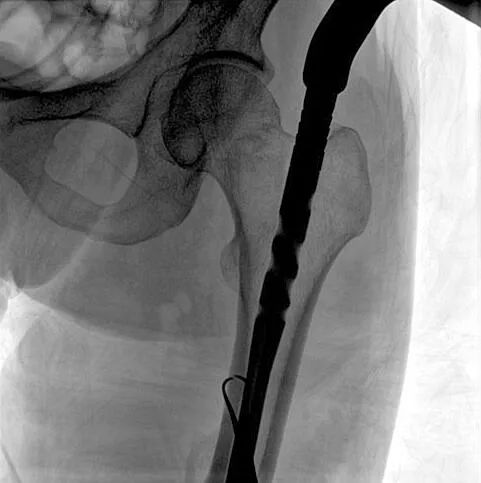

術(shù)中使用普愛醫(yī)療大平板一體式C形臂進行透視,判斷骨折情況及克氏針、髓內(nèi)釘?shù)冉饘僦踩胛锏奈恢茫M行調(diào)整。C形臂準確的術(shù)中定位,大大縮短了手術(shù)的時間,減輕了患者的痛苦,輔助手術(shù)順利完成。

在進行髓內(nèi)釘內(nèi)固定術(shù)時,醫(yī)生需要同時觀察到入釘點和骨折部位的情況,普愛醫(yī)療大平板一體式C形臂采用30CM×30CM的平板探測器,能夠呈現(xiàn)更廣闊的成像面積,滿足大部分長骨髓內(nèi)釘內(nèi)固定術(shù)的攝片需求。

術(shù)中定位準確、出血量少,術(shù)后影像顯示股骨移位糾正,恢復(fù)良好力線,手術(shù)效果良好。